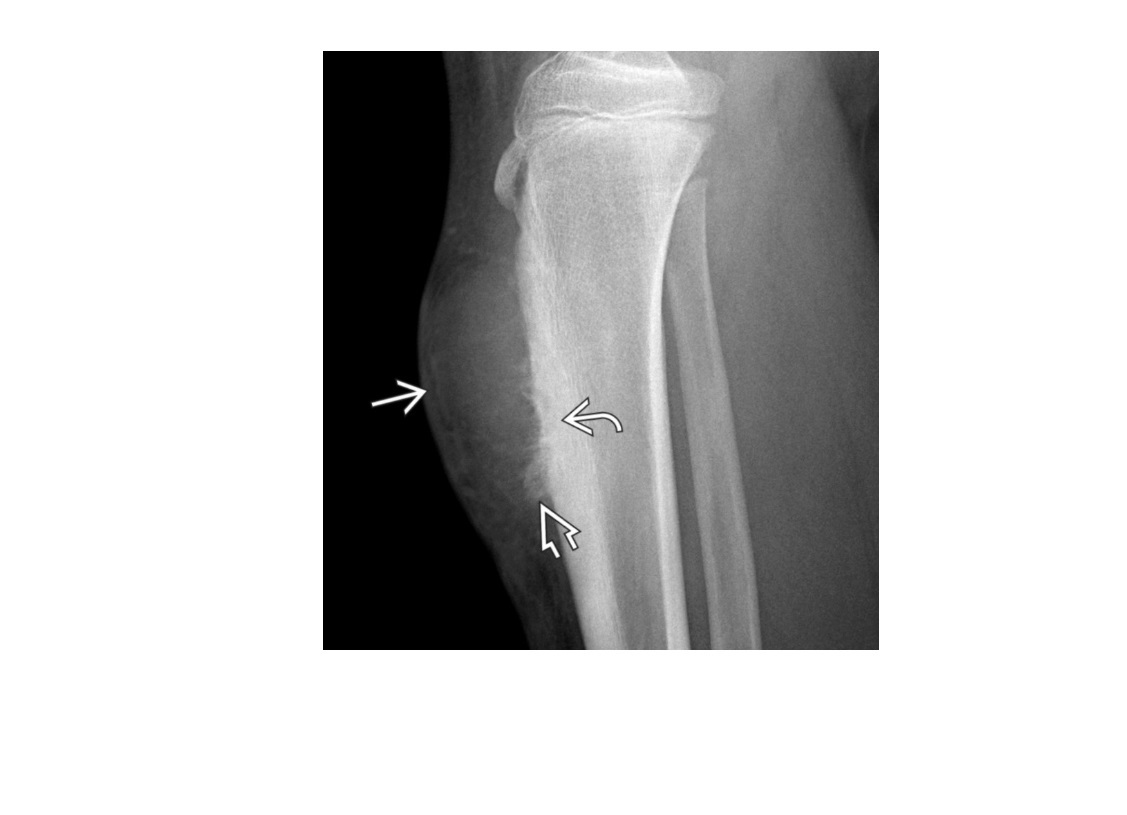

Adamantinoma

Low-grade, malignant lesion most frequently arising in tibial** cortex**

Mutlifocal

slcerotic and lytic compoents

*Cortically based lesion in anterior tibia